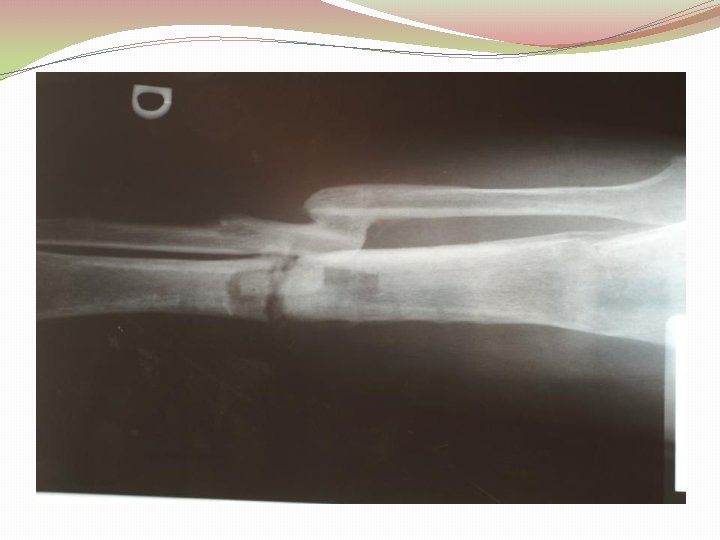

Ķirurģiska ārstēšana Osteomielīta pacientiem jāveic radikāls debridement ķirurģiski, kas ietver visu procesā iesaistīto audu rezekciju: �Mīksto audu rētas rezekcija �Cīpslu kalcinātu rezekcija �Distantu sekvestru rezekcija �Kaula rezekcija līdz vizuāli veseliem audiem – readzama punktveida asiņošana ´Paprika sign’. Bogdan Maciuceanu, Lucian Jiga, Alexandru Nistor, Jenel Marian Pastrascu, Mihail Ionac Chronic Osteomyelitis of Long Bones Timisoaral Medical Jornal, 2005

Ķirurģiska ārstēšana Veiksmīgas ķirurģiskas ārstēšanas stūrakmens ir mirušas telpas ‘Dead space’ aizpildīšana, kas izveidojas pēc debridemet veikšanas Brad Parsons, Elton Strauss, Surgical management of chronic osteomyelitis, The American Journal of Surgery 188 (Suppl to July 2004) 57 S– 66 S